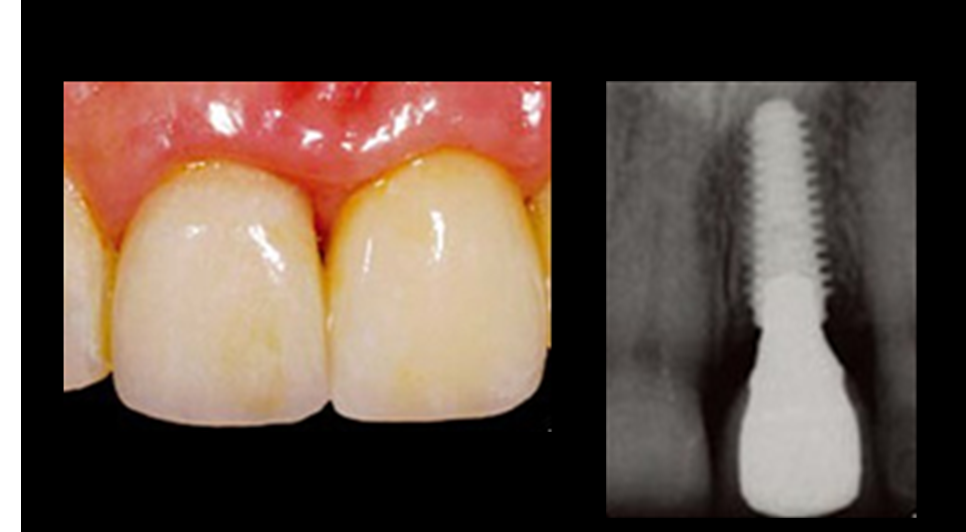

Clinical case: Immediate post-extraction insertion of implant & immediate loading

- Courtesy of Prof. Giuseppe Luongo, Italy -

AnyRidge, immediate loading, single implant, multicenter study, maxillary anterior, Prof. Giuseppe Luongo, single replacement

AnyRidge implant system

Immediate functional loading of single implants: a multicenter study with 4 years of follow-up

/J Dent Res Dent Clin Dent Prospect 2018; 12(1):26-37 | doi: 10.15171/joddd.2018.005

https://www.ncbi.nlm.nih.gov/pubmed/29732018